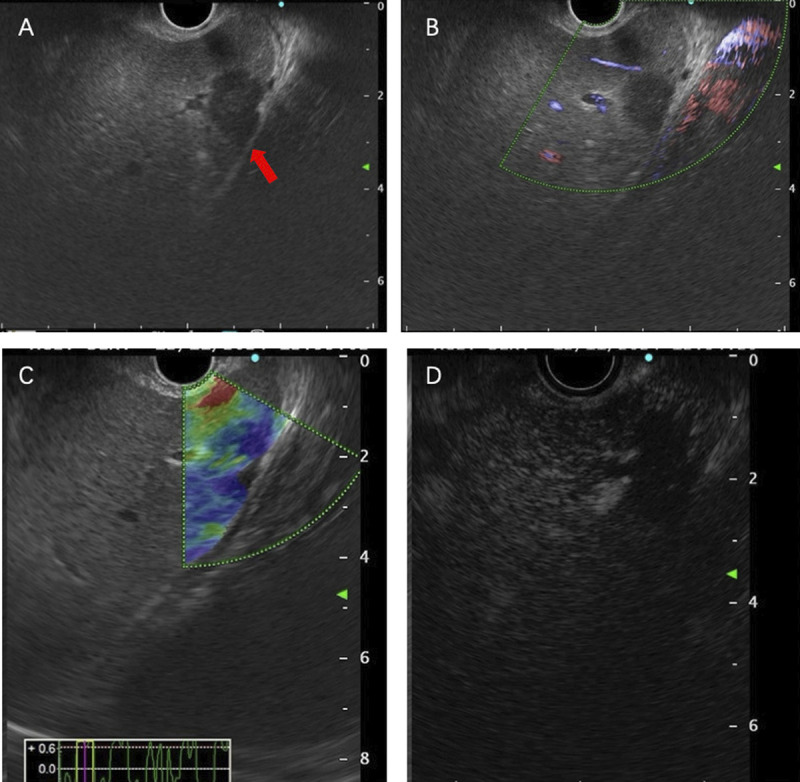

Abstract Image